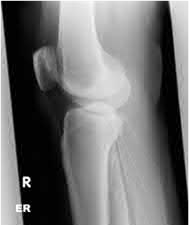

A 34-year-old male falls from a roof and sustains a right elbow dislocation that is closed reduced in the emergency room. An AP radiograph is shown in Figure A. This injury pattern is at highest risk for which of the following?

Anteromedial coronoid facet fracture and LCL injury following an elbow dislocation is commonly associated with varus posteromedial rotatory instability. Varus and posteromedial rotation force on the forearm results in rupture of the LCL from its humeral origin. As the LCL ruptures, the medial coronoid process is fractured as it impacts against and under the medial trochlea. Fracture involvement of the sublime tubercle, where the MCL attaches, can lead to more instability. Ulnar neuropathy can be seen following this injury pattern but AIN and PIN nerve palsy do not commonly characterize this injury pattern.

The review article by O'Driscoll highlights key points in diagnosis and management of capitellum, distal humerus, coronoid, and terrible triad injuries.

The article by Doornberg and Ring is a Level 4 study of 18 patients that sustained varus posteromedial rotational injuries resulting in anteromedial facet coronoid fractures. They found that lack of fixation at injury or malunion of the anteromedial facet were significant predictors of suboptimal functional outcome and development of arthrosis.

The anteromedial facet is highlighted in yellow as displayed in Illustration A. Illustration B depicts the lateral collateral ligament injury also evident during

varus stress fluroscopic examination, due to tension failure of the LCL off its humeral origin during the various mechanism.